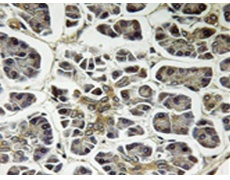

IHC positive control: |

Human pancreas tissue |